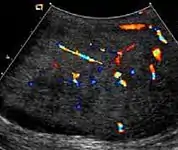

Fibrous pseudotumor

Fibrous pseudotumors, also known as fibromas are thought to be reactive, nonneoplastic lesions. They can occur at any age, about 50% of fibromas are associated with hydrocele, and 30% are associated with a history of trauma or inflammation (Akbar et al., 2003). Although the exact cause of this tumor is not completely understood, it is generally believed that these lesions represent a benign reactive proliferation of inflammatory and fibrous tissue, in response to chronic irritation. Sonographic evaluation generally shows one or more solid nodules arising from the tunica vaginalis, epididymis, spermatic cord and tunica albuginea [Fig. 18]. A hydrocele is frequently present too. The nodules may appear hypoechoic or hyperechoic, depending on the amount of collagen or fibroblast present. Acoustic shadowing may occur in the absence of calcification due to the dense collagen component of this tumor. With color Doppler sonography, a small to moderate amount of vascularity may be seen [Fig. 19].

Fig. 18. Fibrous pseudotumor. A homogeneous hypoechoic nodular lesion is seen attached to the tunica associated with minimal amount of hydrocele.

Fig. 19. Fibrous pseudotumor. With color Doppler, a little vascular flow is seen in this fibrous pseudotumor.